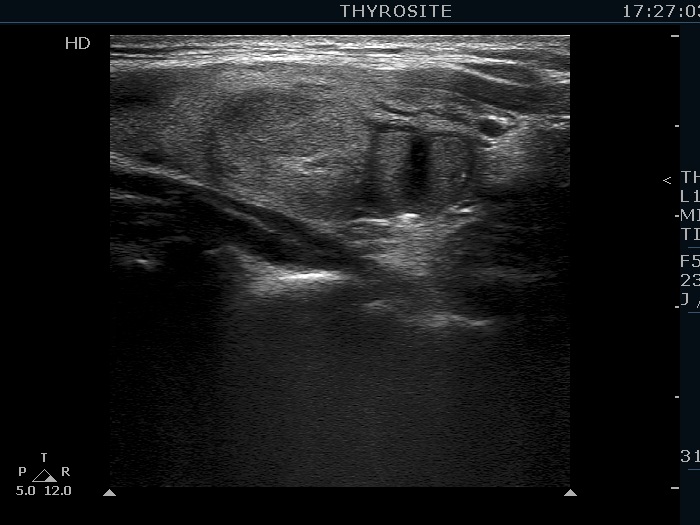

The composition of the nodule - case 956 (ultrasonographic picture 8)

Left lobe, longitudinal scan - after the removal of 2 mL serous cystic fluid. On this view, the lower nodule should be categorized as a central type cystic nodule.